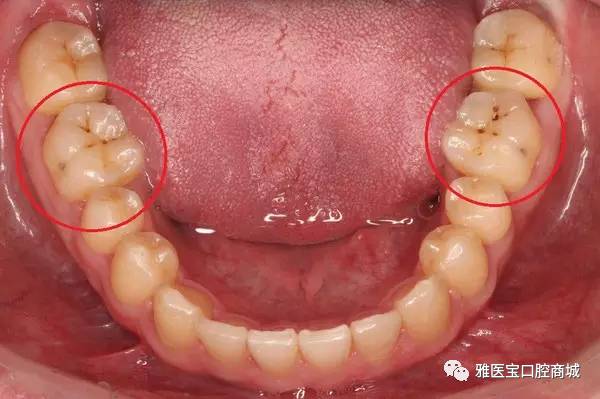

3、色素沉着与龋齿:长期食用含有色素的食品或饮料,如咖啡、茶、红酒等,可能会导致牙齿色素沉着,龋齿也可能导致牙齿变黑并产生疼痛。

3、牙齿美白与修复:对于因色素沉着和龋齿导致的牙齿变黑,可以通过牙齿美白或修复的方法来治疗,可以使用牙齿漂白剂或进行牙齿贴面。